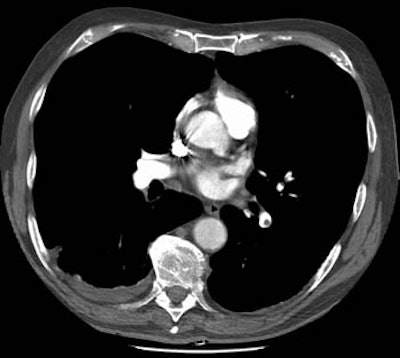

Clot is evident as a filling defect in the left lower lobe pulmonary artery.